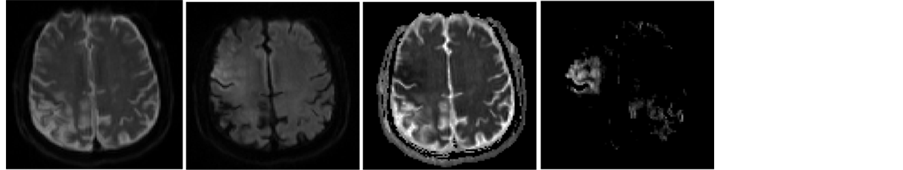

To alleviate the interference of normal brain tissues and speed up the calculation, candidate infarcts in the form of regions of interest (ROIs) are extracted from thresholding ADC maps subjected to DWI [5]. Specifically, denote the most frequent ADC value for all voxels within the brain as ADCref, any voxels with ADC not greater than 0.75*ADCref are to formulate connected components. Any connected components with average DWI values not smaller than the intensity average plus the intensity standard deviation of brain voxels on DWI at the corresponding axial slice are kept as part of region R1. Voxels with ADC value within (0.75*ADCref, 0.85*ADCref] are checked to formulate connected components and added to R1 if the components has at least one neighboring voxels in R1. R1 is then increased by morphological dilation with a structuring element of radius Rd (being 2 voxels). Suppose the z coordinates of R1 are in the range of z0 to zn with zn >= z0, then R1 region on the axial slice z0 and zn are respectively pasted to axial slice z0 − 1 and zn + 1 to attain the eventual ROIs. Figure 3 shows an axial slice of DWI, ADC and the corresponding ROIs (in color), where regions in red are initial ischemic infarcts and those in yellow are added voxels through the described morphological dilation.

Figure 3. From left to right, an axial slice of DWI, ADC, the segmented ischemic regions form [5] on DWI and the corresponding ROIs for detecting infarction overlaid in color on DWI, where the region in red are initial ROIs from [5] while those in yellow are from morphological dilation.